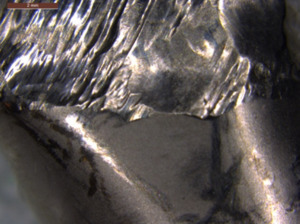

The microscopic observations of the head surface of the endoprosthesis made of the CoCrMo alloy indicate that the worn head surface showed typical features of abrasive wear (Fig. 17). The relatively deep abrasive grooves near the edges of the worn surface can be observed in the low magnification of the SEM images. Microploughing is the dominant erosion mechanism caused by hard third-body particles, in which the material is not removed from the surface but moves to the side of the erosion groove.40However, macroscopically, the wear features showed different damage characteristics due to differences in the local contact pressure. The extent and shapes of the wear grooves indicate a significant difference in the movements and size of the abrasive particle.41,42 Those detached particles could form third bodies and be rejected from the contact or spread on the metal surface. Topographic measurements were used to describe wear. Analyses performed on the surface, shown in Figure 18, indicate that the depth of these scratches was up to approximately 2 µm. A representative measurement taken along one of the lines is shown in Figure 18c.